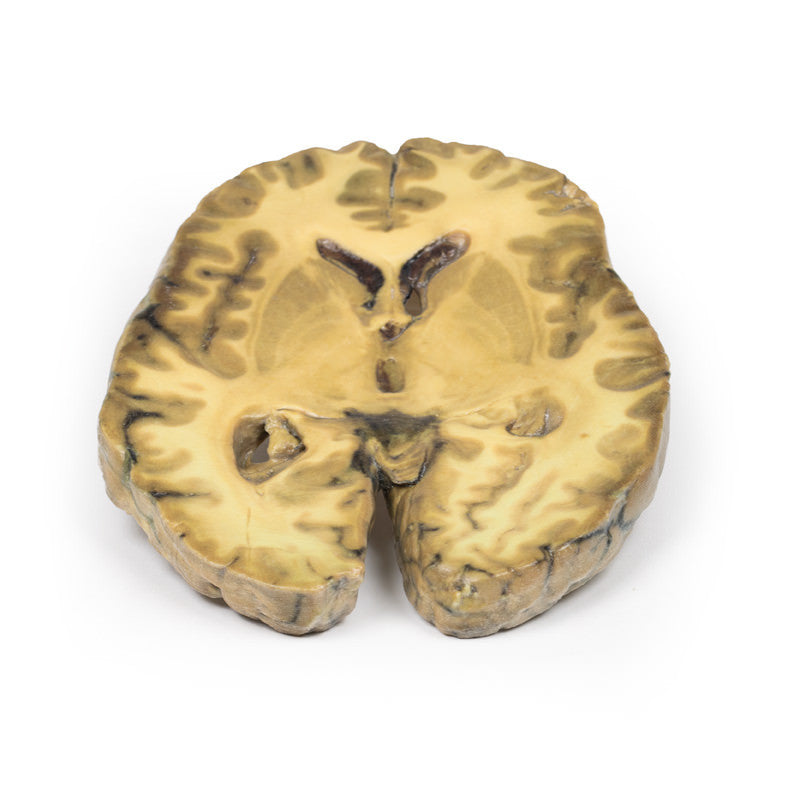

This specimen is an example of ventriculitis, with pneumococcal meningitis and right basal pneumonia also being found at autopsy. The horizontal slice through both cerebral hemispheres displays both of the lateral ventricles. The ventricles show a thickened, rough ependymal lining with cellular debris accumulation around the choroid plexus and also in the anterior horn. The lower surface shows similar changes and also displays the normal arrangement of the caudate nucleus, lentiform nucleus and internal capsule. Histology demonstrated extensive infiltration of neutrophils in the sub-arachnoid space as well as multifocal severe (sub)endothelial infiltration with obstruction of vascular lumen and involvement of the blood vessel walls. The inflammation extended into the cerebral parenchyma causing haemorrhage and necrosis.